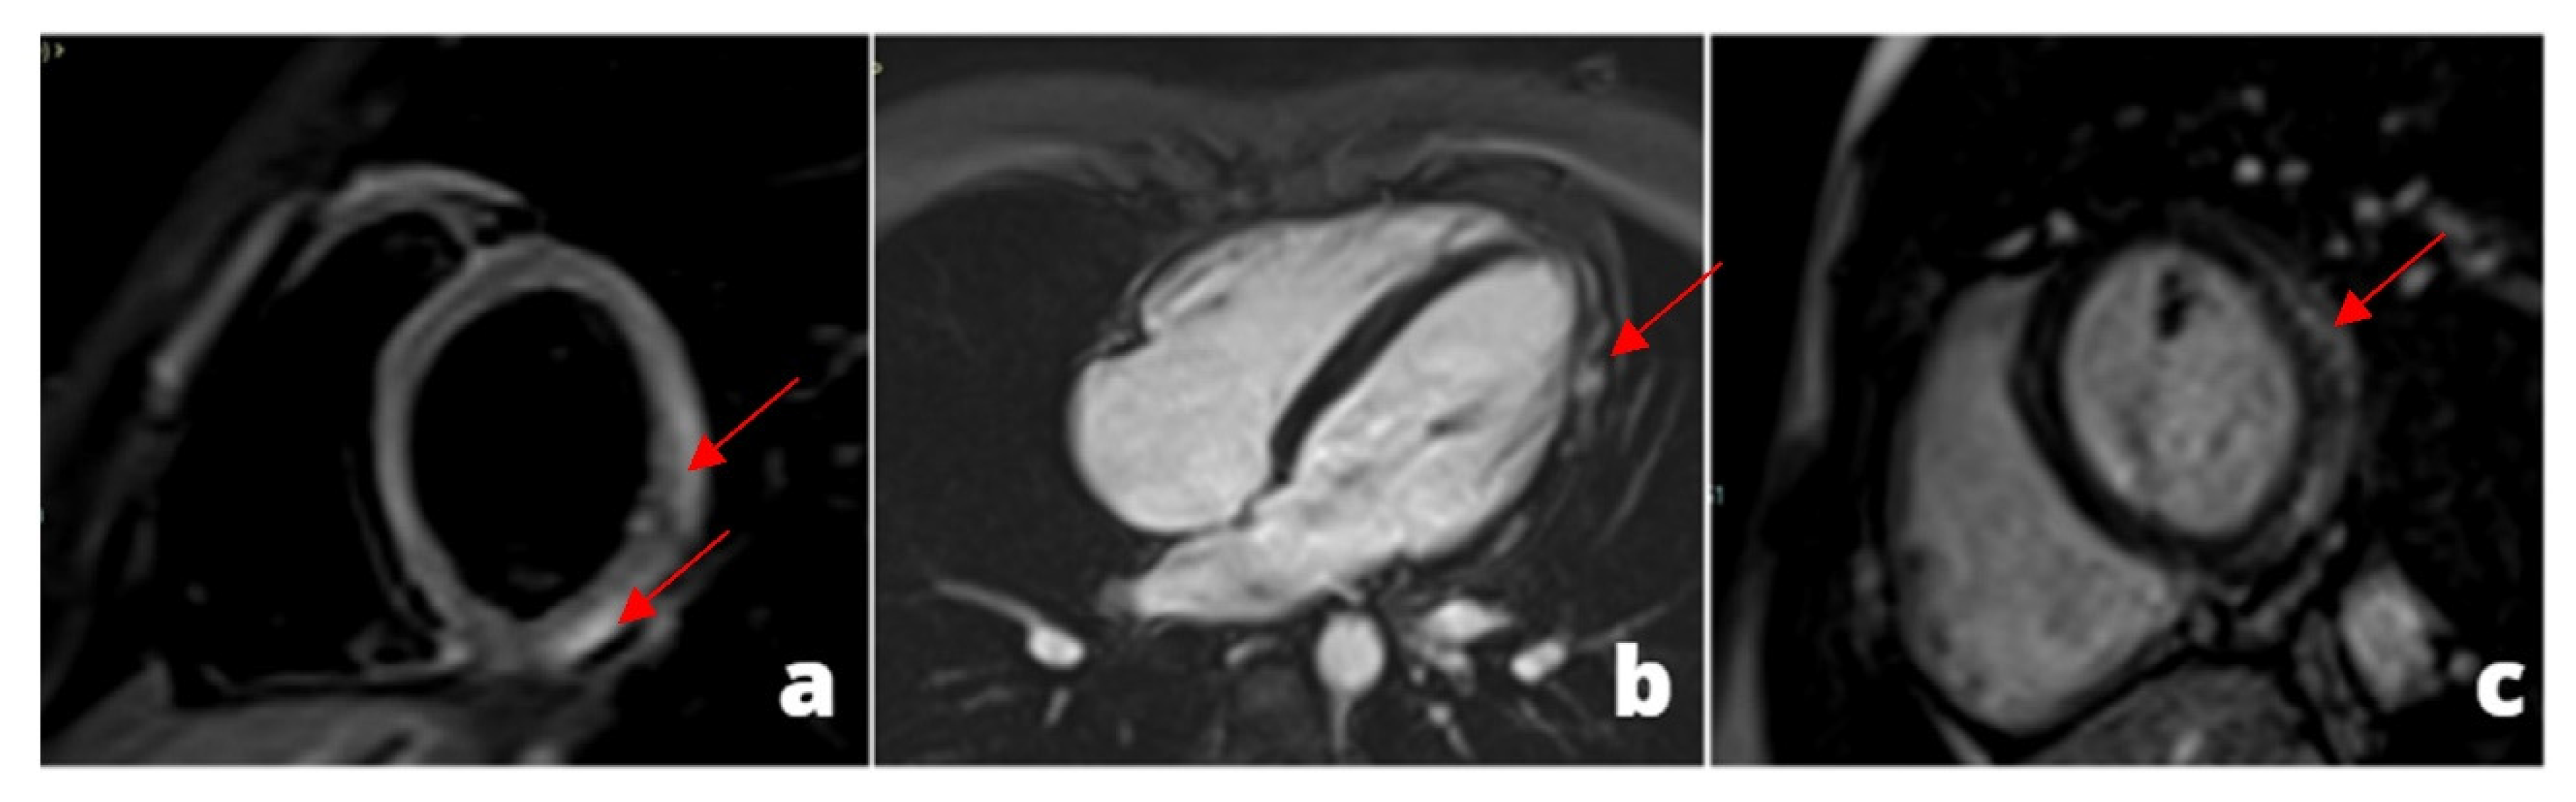

Figure 6. Patient with chest pain and dyspnea for more than 10 days with recent worsening of symptoms. CT shows the presence of massive bilateral pulmonary thrombo-embolism (red arrows) in the right and left lower lobe pulmonary artery (a). Secondary overload of the right-side circulation: enlargement of the right ventricle (c) and secondary tricuspid insufficiency (b).